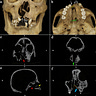

The skull tells you something is wrong before you know what to call it. The right side of the primary palate is incomplete. The alveolar arch has a gap where bone should be. The nasal septum veers sharply to one side. An upper incisor never formed. The face, in life, would have been visibly, unmistakably different.

Macroscopic examination and CT imaging, carried out by Dr. Xiaofan Sun and colleagues and published in the International Journal of Osteoarchaeology,1 confirmed what the morphology suggested: M234-2 was born with unilateral cleft lip and bilateral cleft palate. The defect arises during fetal development, when the tissues forming the lip and palate fail to fuse properly. It is among the most common congenital craniofacial conditions in humans, but its archaeological record is sparse, and in China it was previously unattested entirely. This is the first identified case.